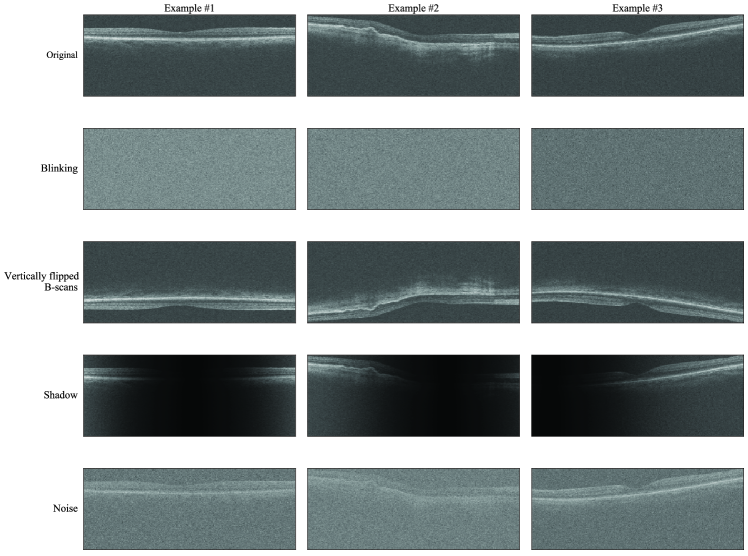

Refer to caption

Figure 3: Examples of artificial artifacts. Each row shows the middle B-scans of a random OCT volume from Ttest. The image in the first row is the original, unaltered B-scan. The other rows each depict a different artificial artifact applied to that B-scan.

To demonstrate the effect of UBIX more clearly, we performed experiments where we artificially corrupted the dataset with artifacts that also occur naturally in OCT scans. The different artifact types were blinking artifacts, vertically flipped B-scans, shadows and noise. Fig. 3 shows a number of examples. We gradually introduced more OCT volumes with artificial artifacts and compared the performance for UBIX, UBIX with δ=𝛿\delta=\infty and MIL.

Vertically flipped B-scans are caused by a Fourier-domain detection artifact, as described by [48]. Shadows and noise are usually caused by media opacities, such as corneal scarring and cataract. The artificial artifacts were implemented as follows:

• B-scans with artificial blinking artifacts were generated by taking an image in which all pixel values are 0 to which we applied additive random Gaussian noise for which the mean was the median pixel value in the full OCT scan and the standard deviation was equal to the standard deviation of the OCT scan.

• The vertically flipped B-scans were generated by flipping the B-scans along the horizontal axis.

• The noise artifact is Gaussian noise added to the original image with a mean of 00 and a standard deviation of 444 times the standard deviation within the original OCT volume.